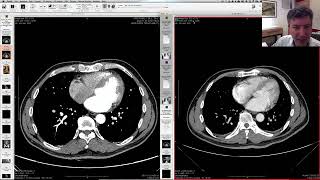

Estenose de carótida na angioTC com OsiriX: NASET/ECST e casos clínicos.